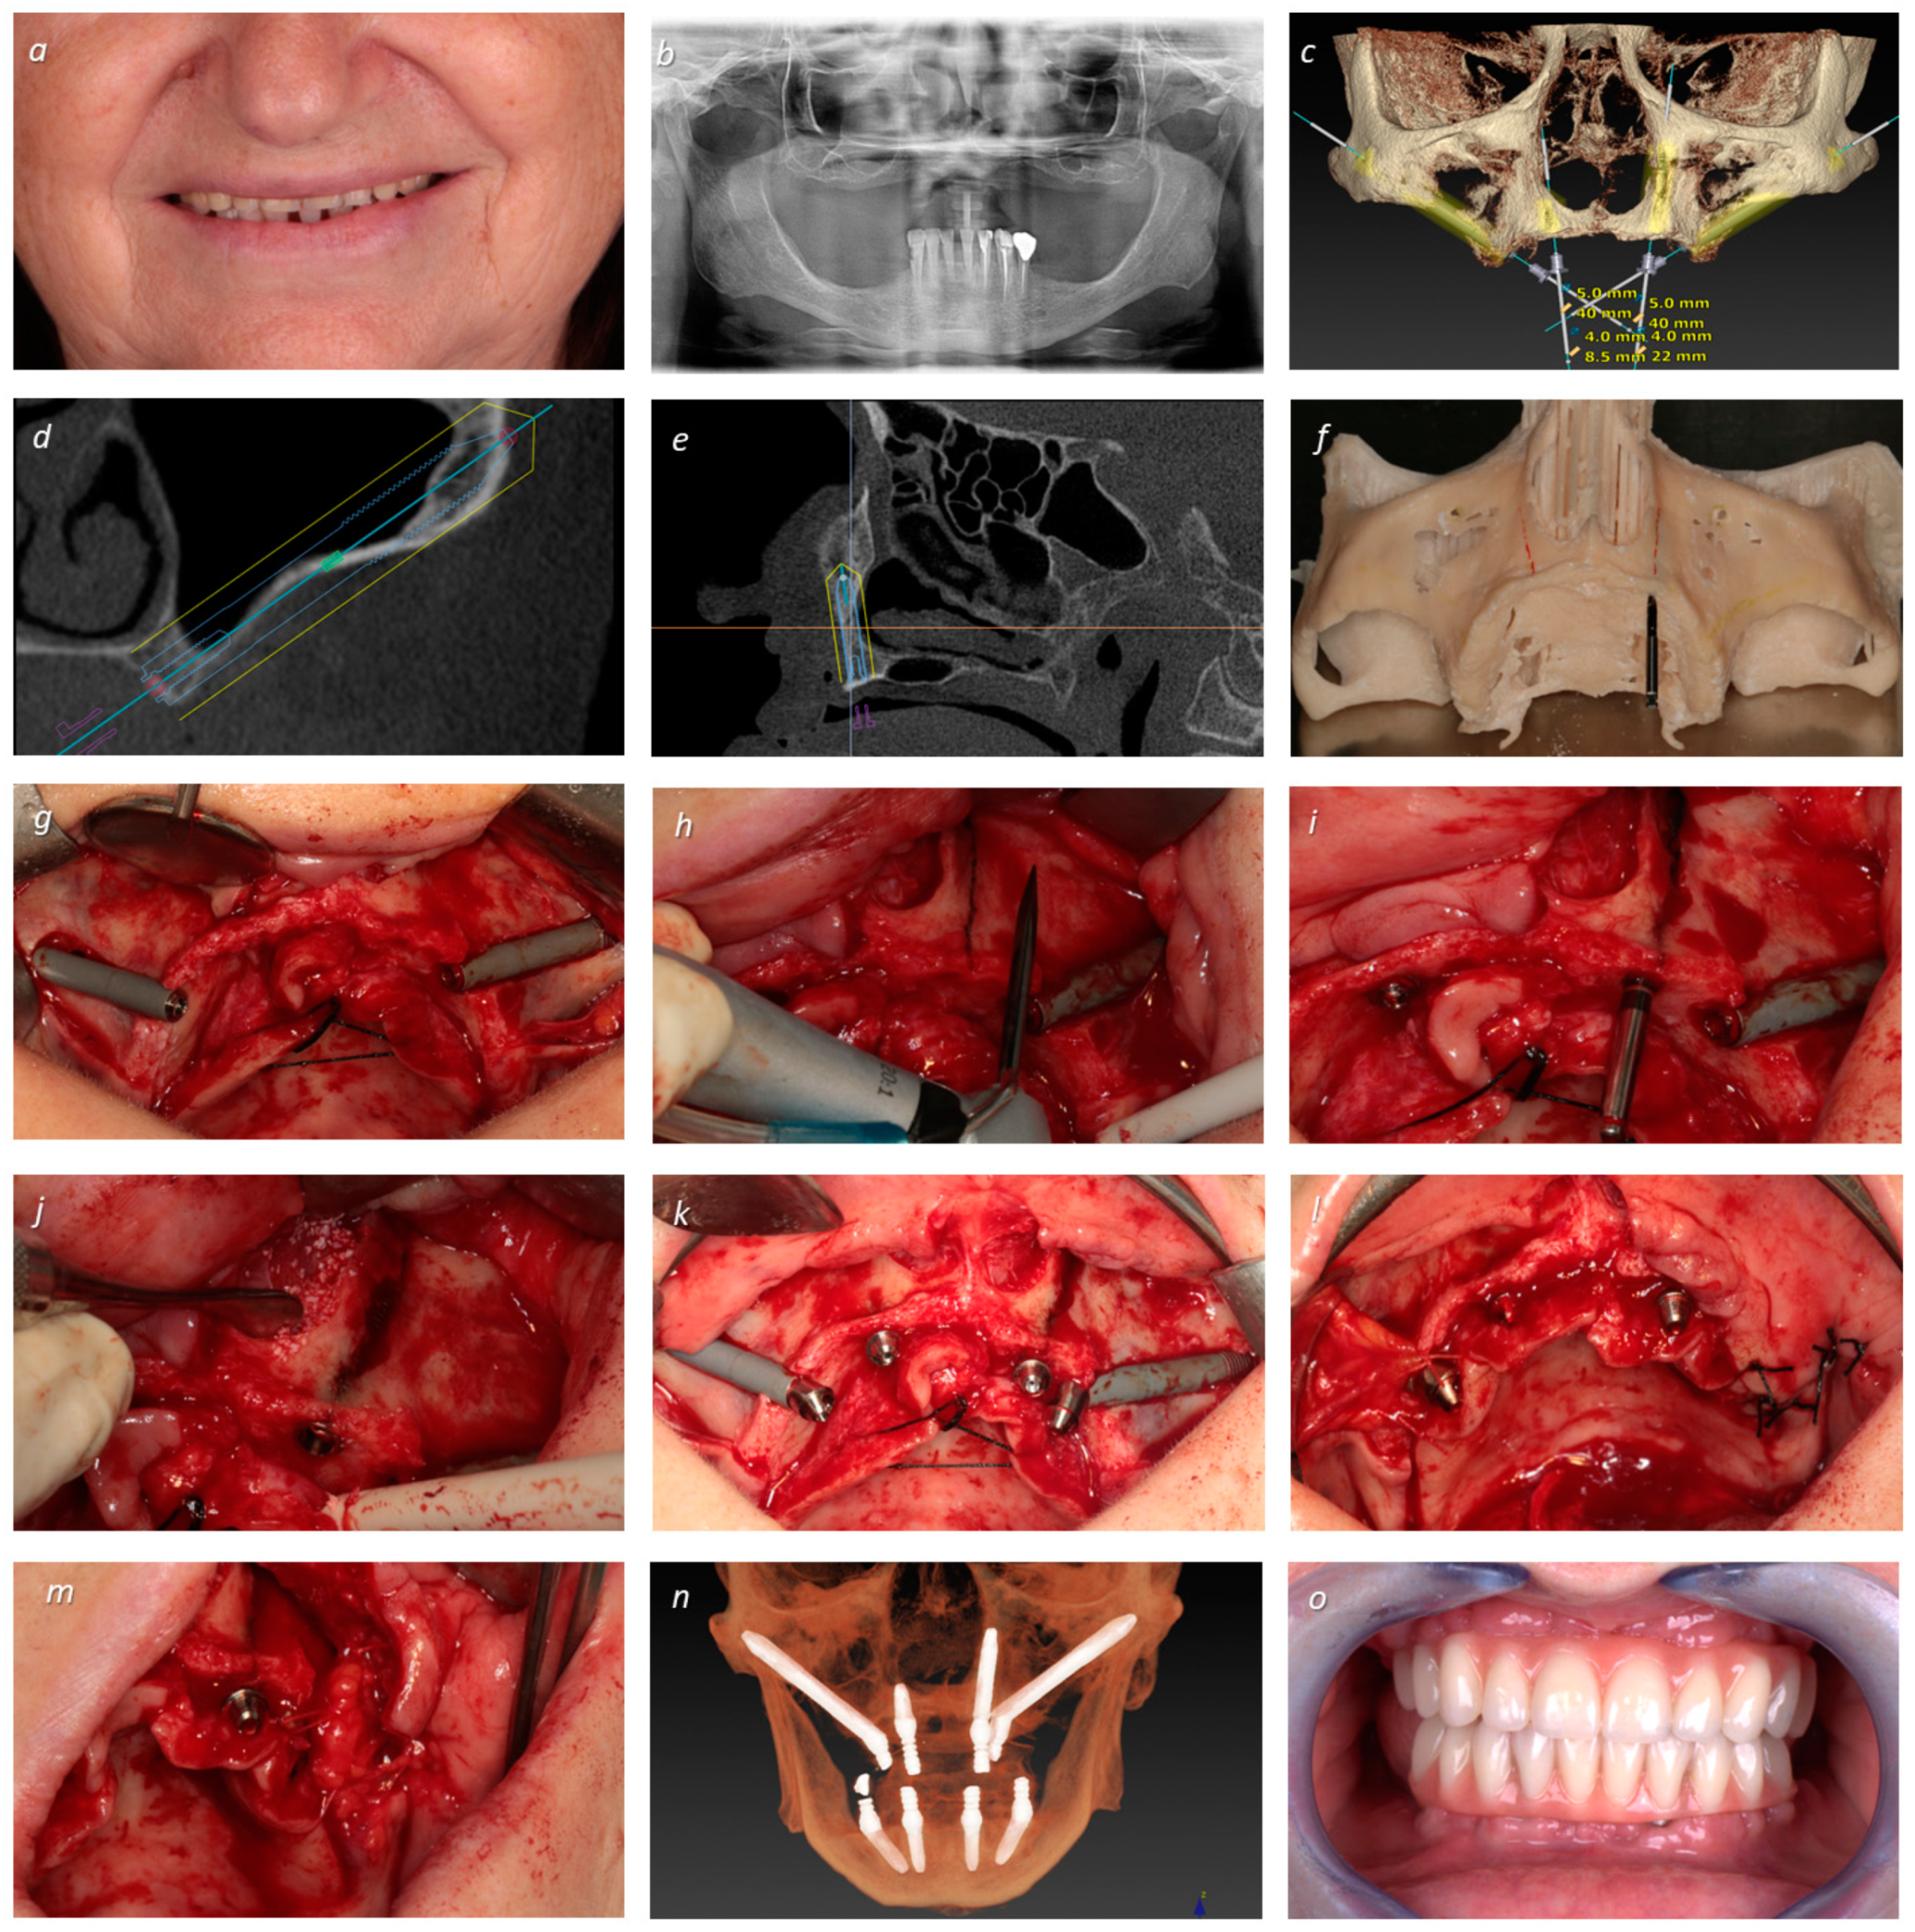

| 1 | EM 0° 5 × 40 | S 4 × 8.5 | T 3.75 × 22.5 | EM 0° 5 × 40 | 66 | F | 3 | I | NG | +50 |